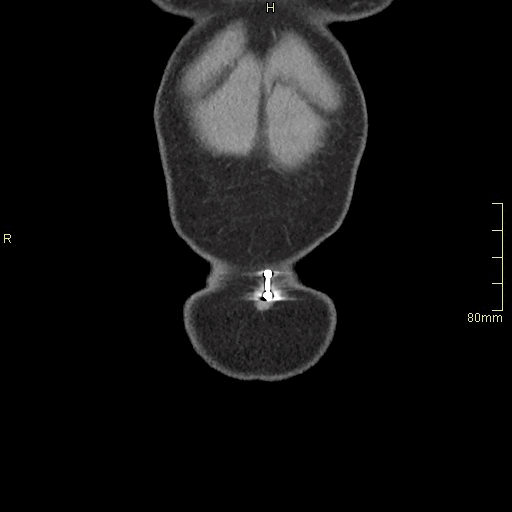

CTPA (Coronal)

Portal Venous Abdomen (Coronal)